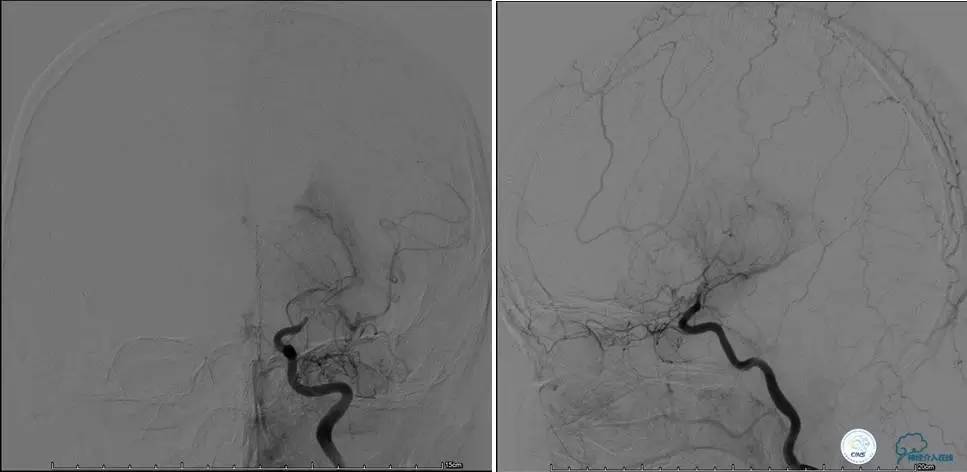

造影评价血管、判断闭塞段,微导丝小心穿过闭塞段,微导管造影,交换技术,球囊扩张,Enterprise支架。在后扩张时导丝刺破M3段血管,蛛网膜下腔出血(SAH)。

微导管进入破裂血管,栓塞弹簧圈1枚,出血停止,结束手术。继续双抗,术后2天肌力2级,神经功能恢复明显加快。

术后即刻和6天后CT,患者无明显临床症状。

半年后复查造影,无支架内再狭窄,可见弹簧圈,患者恢复至自己柱杖行走。